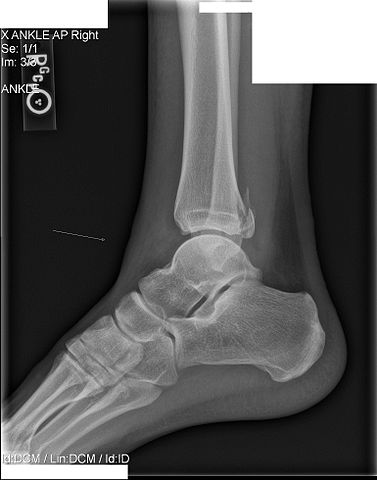

[[File:Maisonneuve fracture.jpg]] | |||

Image